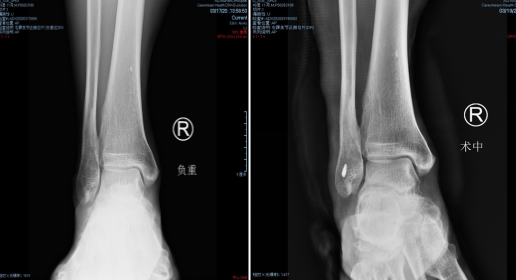

上周,足踝科大科主任石荣剑主任医师率领团队以精湛的技术完成两例微创手术,术后效果突出,赢得患者赞誉:采用第三代微创踇外翻矫正技术,为一位踇外翻畸形10多年的57岁患者成功进行了左右足矫正;利用踝关节镜,为一位扭伤右踝半年的49岁患者进行了镜下关节探查清理+距腓前韧带修复手术。

石院长给他做了仔细检查,结合片子,确诊为“右踝外侧韧带损伤”。两天后,石院长李亮医生给患者进行了踝关节镜下右踝探查清理+距腓前韧带修复手术。

术中,探查见关节腔大量增生病变滑膜组织,距骨软骨面多处软骨剥脱变性,明显的外侧副韧带损伤后继发关节炎表现。手术医生在踝关节镜下刨削刺激病变的距骨软骨,打入锚钉固定距腓前韧带,圆满完成手术。

踝关节镜技术是治疗踝部关节损伤与疾病的重要手段,具有损伤小、恢复快、并发症少等优点。sararz足踝外科以成熟的技术开展足踝部骨折脱位及运动损伤的踝关节镜微创治疗,包括:踝关节滑膜炎以及各种关节炎;踝关节滑膜软骨瘤;踝关节撞击综合征;踝关节不稳定;距骨软骨损伤;内踝骨折、后踝骨折、距骨骨折、跟骨骨折;踝关节融合、距下关节融合、踝管综合征等治疗。